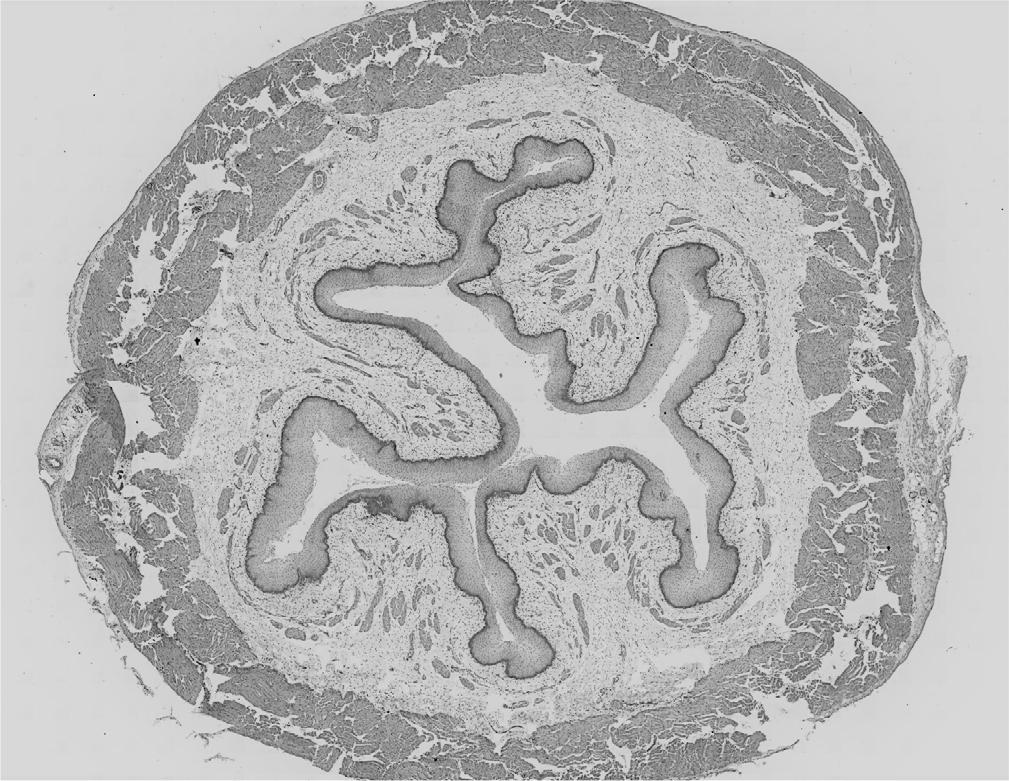

Fig. 1.

Fig. 2.

Fig. 3.

Fig. 4.